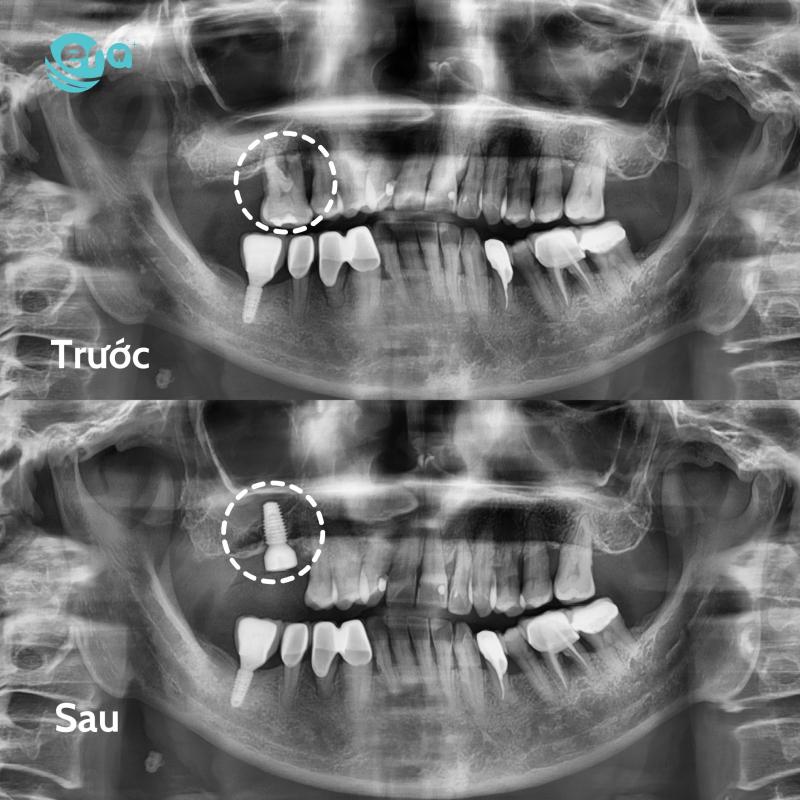

Nha Khoa ERA

Gọi điệnGiữa muôn vàn lựa chọn trong lĩnh vực chăm sóc răng miệng, Nha Khoa ERA tại phường Bình Đông vẫn luôn là điểm đến được đông đảo khách hàng tin tưởng nhờ vào sự chuyên nghiệp, tận tâm và chất lượng vượt trội trong từng dịch vụ.

Với định hướng trở thành “điểm tựa nụ cười Việt”, ERA không ngừng đổi mới và nâng cấp toàn diện từ đội ngũ nhân sự, công nghệ điều trị đến không gian khám chữa bệnh. Mỗi khách hàng khi đến với ERA đều được trải nghiệm quy trình thăm khám bài bản, rõ ràng và cá nhân hóa theo từng nhu cầu cụ thể.

- Công nghệ hiện đại: Máy X-quang kỹ thuật số, máy siêu âm Piezotome nhổ răng không đau, công nghệ thiết kế nụ cười 3D giúp tăng độ chính xác và giảm thiểu xâm lấn